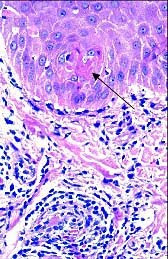

7. Histología

- Se han descrito dos patrones:

• Perniosis superficial: Edema en dermis papilar y marcado infiltrado mononuclear perivascular en la dermis superior. El infiltrado mononuclear puede comprometer la pared del vaso, sugiriendo una vasculitis linfocítica.

• Perniosis profunda: El infiltrado perivascular se extiende hasta el tejido celular subcutáneo.

La biopsia, innecesaria en este caso dado que el diagnóstico es eminentemente clínico, evidenció linfocitos perivasculares con fibrina intravascular, indicativos de formación temprana de trombo.